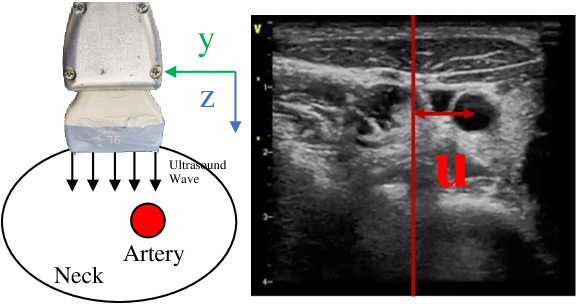

where ρ\rho is a scaling factor, and the gradient 𝒂ku\nabla_{\bm{a}^{k}}u can be obtained by the imaging principle of ultrasound. For a linear array probe that performs a straight-line scan (see Fig. 2(b)), the mapping is linear:

Δy=aΔu,\Delta y=a\Delta u, (6)

where aa is a known probe parameter, Δy\Delta y is a displacement of the probe in cartesian yy axis, Δu\Delta u is the difference of pixel position of the artery. From (6), we can get a constant gradient. Hence the guidance made every sample towards the position centering the carotid in the ultrasound image.

To maintain a steady and comfortable contact between the probe and the patient’s neck, the force along the zz axis is assigned to be force controlled (see Fig. 2), so the selection matrix for force is 𝑺fee=diag([0,0,1,0,0,0]){}^{ee}\bm{S}_{f}=diag([0,0,1,0,0,0]), and the remaining dimensions are controlled with impedance; the selection matrix for impedance is 𝑺iee=diag([1,1,0,1,1,1]){}^{ee}\bm{S}_{i}=diag([1,1,0,1,1,1]). After transformation, the selection matrix in base frame used in the main task controller (9) 𝑺i,𝑺f\bm{S}_{i},\bm{S}_{f} is obtained.